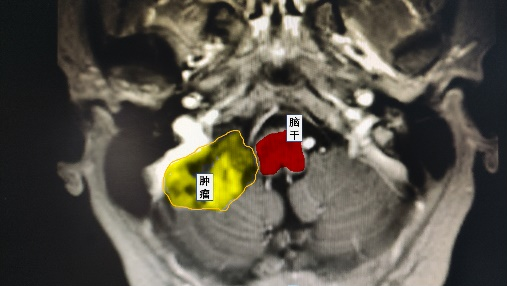

近日,鄰玉鎮(zhèn)楊女士在做體檢時(shí)意外發(fā)現(xiàn)“小腦占位”,緊貼腦干的兇險(xiǎn)位置,讓她感到驚恐和困惑。幸運(yùn)的是,她了解到瀘州市中醫(yī)醫(yī)院神經(jīng)外科與華西醫(yī)院合作,具有一流的醫(yī)療水平,便前往尋求專(zhuān)業(yè)的診治。

根據(jù)術(shù)前的規(guī)劃,謝勇主任通過(guò)使用神經(jīng)外科顯微鏡成功暴露出了小腦腫瘤組織,并與華西教授共同切除了緊貼著腦干和包繞顱底顱神經(jīng)的腫瘤組織。術(shù)后患者無(wú)神經(jīng)功能障礙,順利出院。